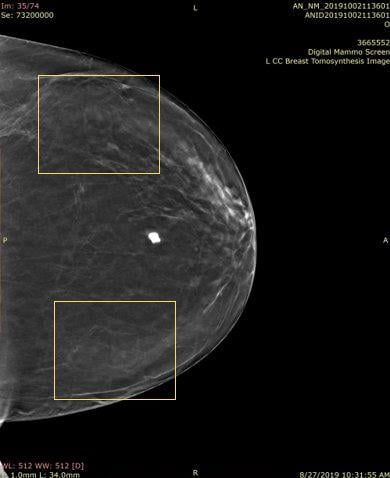

As radiologists reviewed the 3-D images, they began to realize that dense objects, such as calcifications, biopsy clips, surgical clips and the numerous skin markers that they had been using could generate artifacts that made interpreting the images harder.

In particular, because they are larger than calcifications and clips, the skin markers3 that were used to indicate skin lesions, scars, sites of a palpable mass or pain caused significant artifacts called a ring down effect that caused distractions and limited visibility of underlying tissues.

“The biggest problem with the 2-D markers being used on the 3-D examinations is the ‘ring-down’ or ‘slinky effect’ that actually limits visualization of adjacent and underlying tissues, and is distracting, making one look at the artifact instead of the adjacent tissues,” she explained.

Responsive to customer needs, Beekley Medical partnered with early adopters of 3-D mammography to develop mammographic skin markers that would image well in order to convey critical information of surgical scar location, skin lesions, palpable areas, and other areas of concern under both the 2-D and 3-D portions of the DBT exam with minimal-to-no “slinky” artifact. Field-tested TomoSPOT skin markers for 3-D digital breast tomosynthesis were introduced in 2014 — the first markers specifically made for DBT technology.

According to Baum, “The 3-D markers as seen on the 2-D images are less bright, and also less distracting, when reviewing these images. They don’t have all the lines the old one had (referring to 2-D markers). The old ones had marks all the way through the breast. The lines with these (3-D markers) are less bright and you can still see the tissue through it. I don’t have to go through the images 2 or 3 times to get around the artifact — it takes longer to look harder in the areas where there is the slinky effect so as not to miss things — especially calcifications. The TomoSPOT skin markers result in a faster reviewing time of the 3-D image for me, as I don’t have to spend extra time looking in the area of the artifacts caused by the old markers.”